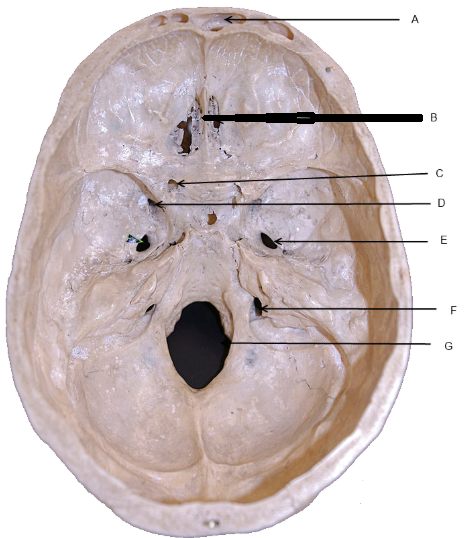

Station Topic: Brain Anatomy – Internal Carotid Artery

You are asked to demonstrate your knowledge of the internal carotid artery (ICA) and its relation to brain anatomy.

Identify and describe the course of the internal carotid artery from the neck to the brain. (5 marks)1 The ICA arises from the common carotid artery at the level of C3–C4 vertebrae.

Cervical segment: Ascends vertically in the neck without branching.

Petrous segment: Enters the carotid canal in the petrous temporal bone; runs anteromedially.

Cavernous segment: Courses through the cavernous sinus; forms an S-shaped curve (the carotid siphon).

Cerebral (supraclinoid) segment: Exits the cavernous sinus and pierces the dura mater at the roof of the cavernous sinus to enter the subarachnoid space; gives terminal branches to the brain.